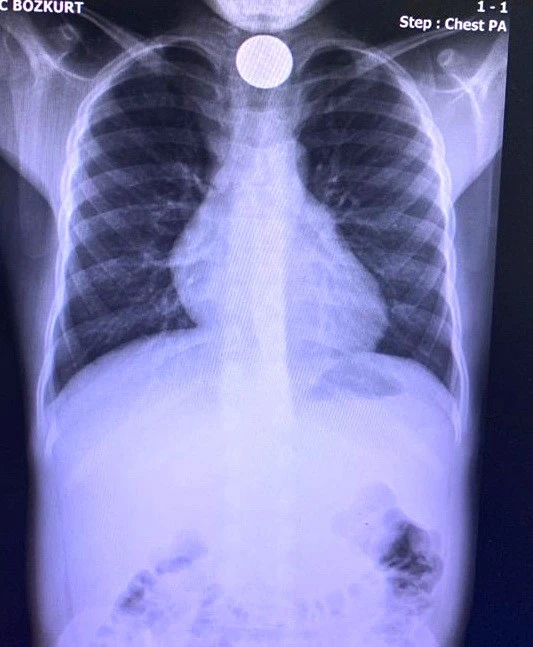

Olay, Kahta ilçesi Yeni Mahalle 110 nolu sokakta meydana geldi. 9 yaşındaki M.M.B. evde madeni para ile oynarken parayı yuttu. Annesine madeni 1 lira yuttuğunu söyleyen çocuk, annesinin 112 sağlık ekiplerine haber vermesi üzerine eve gelen sağlık ekipleri tarafından Kahta Devlet Hastanesi acil servisine kaldırıldı. Çocuğun yuttuğu para, röntgende tespit edildi. Acil serviste yapılan müdahalelere rağmen doktorlar madeni parayı çıkartamadı. Bunun üzerine çocuk, boğazında takılı kalan madeni paranın çıkarılması için Adıyaman Eğitim Araştırma Hastanesine sevk edildi. Çocuğun ameliyata alınacağı öğrenildi.